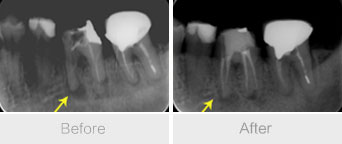

牙齿深龋或者得了牙髓炎要进行根管治疗,根管治疗是牙科临床上治疗牙齿病变有效的方法。做根管治疗可以停止炎症的发展,尽可能保留患牙。那么要做根管治疗需要多少钱呢?

康贝佳口腔采用的根管治疗是目前保存患牙较好的治疗方法,成功率高,针对牙齿、牙髓、根尖病变的治疗方法,也是残根、残冠得以保留的方法,真正是“救牙工程”。>>>在线咨询,根管治疗需要注意哪些?>>>